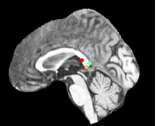

Datasets: A set of isotropic mm MR scans were obtained from the ADNI database [10] to evaluate the proposed method. While, a subset of and images are used for training and testing. All brain images were skull stripped and affinely aligned to the MNI space, thus allowing ground truth planes to be extracted in the standard directions. For cardiac images, we use short-axis cardiac MR of resolution mm obtained from the UK Digital Heart Project [8]. A subset of and images are used for training and testing. ACPC planes are evaluated using the AC and PC landmarks for the distance error calculation. Similarly, we use the outer aspect, inferior tip and inner aspect points of splenium of corpus callosum for mid-sagittal planes. For cardiac MRI, we use six landmarks projected on the 4-chamber plane; the two right ventricle (RV) insertion points, right and left ventricles (LV) lateral wall turning points, apex, and the center of the mitral valve, See Fig. 2.

Results: During inference, the environment samples a plane and the agent updates sequentially new plane’s parameters until reaching the terminal state. In order to have a fair comparison between different variants of the proposed method, we fix the initial plane for all models during evaluation. Table 1 shows the results from these comparative experiments. All methods share similar performance including speed and accuracy, and there is no unique winner for the best overall method. Best performing agents for detecting the mid-sagittal and ACPC planes achieve accuracy of mm and , and mm and , respectively. Where in cardiac, the task is more complex due to the lower quality and higher variability between different scans. The agent has to navigate in a bigger field of view compared to brain images. Thus Duel DQN-based architectures achieve the best results for detecting the 4-chamber plane with mm and accuracy, as a result from learning a better state value function by decoupling it from action-value function. These results are better than the state-of-the-art [6], which achieves an accuracy of mm and . Unlike [6], our method does not require manual annotation of landmarks. More visualization results are published on our github.